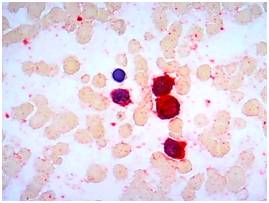

一、检测项目:免疫细胞化学染色(CD41a)

六、染色示例: